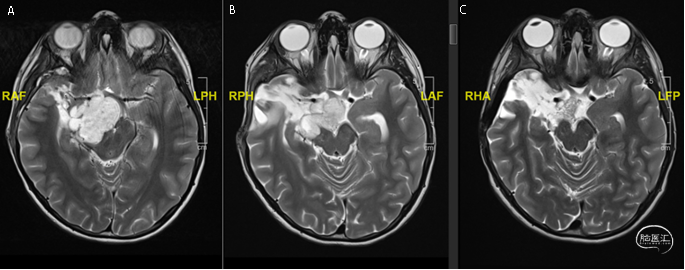

NEJM:ALK融合阳性高级别胶质瘤术前新辅靶向达到手术全切

入院MRI示:左侧颞枕叶巨大占位,中线移位明显,脑室明显受压,无法手术全切。肿瘤存在SPECC1L-ALK融合突变。启动劳拉替尼治疗,剂量为每平方米体表面积95mg,每日一次。患儿肿瘤不断缩小,随后进行手术达到手术全切。